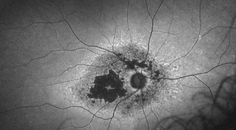

A diagnosis of intermediate AMD includes patients with multiple medium drusen, at least one large druse (>125 μm or the approximate size of a vessel coming off the optic nerve), and/or non-center involving geographic atrophy. Depending on the extent of drusen formation and RPE abnormalities, patients may develop mild visual changes, such as metamorphopsia or reduced visual acuity. These are the patients for whom proper intervention can have a tremendous effect on preserving vision. In addition to routine dilated examinations, OCT imaging and fundus photos are valuable diagnostic tools for identifying the intermediate AMD stage.

In the case of the patient mentioned at the beginning of this article, OCT imaging was acquired and multiple drusen with irregular RPE were noted (Figure 1). We directed the patient to begin taking AREDS2 vitamins and to return for planned routine eye examinations every 6 months. We referred her to the Notal Vision Monitoring Center (Notal Vision) for home monitoring between in-office visits.